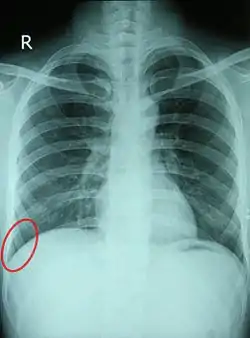

![]() Chest X-ray of a 30-year-old healthy man, with the costodiaphragmatic recess label in red ellipse | |

Pleural effusions collect in the costodiaphragmatic recess when in standing position,[2] and present on plain X-rays as "blunting" of the costophrenic angle.

In anatomy, the costophrenic angles are the places where the diaphragm (-phrenic) meets the ribs (costo-).

Each costophrenic angle can normally be seen as on chest x-ray as a sharply-pointed, downward indentation (dark) between each hemi-diaphragm (white) and the adjacent chest wall (white). A small portion of each lung normally reaches into the costophrenic angle. The normal angle usually measures thirty degrees.

Pleural effusion

With pleural effusion, fluid often builds up in the costophrenic angle (due to gravity). This can push the lung upwards, resulting in "blunting" of the costophrenic angle. The posterior angle is the deepest. Obtuse angulation is sign of disease.

Chest x-ray is the first test done to confirm the presence of pleural fluid. The lateral upright chest x-ray should be examined when a pleural effusion is suspected. In an upright x-ray, 75 mL of fluid blunts the posterior costophrenic angle. Blunting of the lateral costophrenic angle usually requires about 175 mL but may take as much as 500 mL. Larger pleural effusions opacify portions of the hemithorax and may cause mediastinal shift; effusions > 4 L may cause complete opacification of the hemithorax and mediastinal shift to the contralateral side.